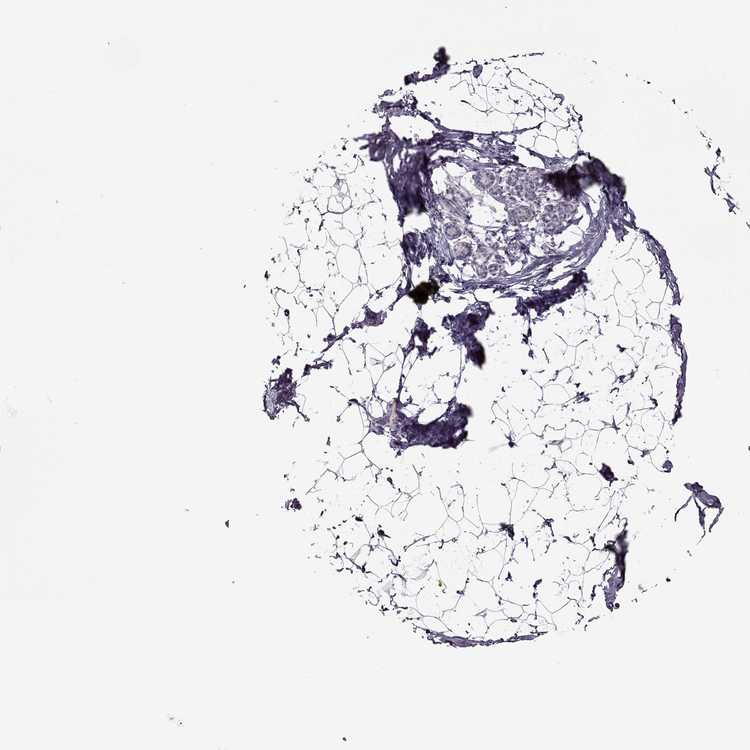

BREAST - Antibody stainingi

Antibody staining in the annotated cell types in the current human tissue is reported as not detected, low, medium, or high, based on conventional immunohistochemistry profiling in selected tissues. This score is based on the combination of the staining intensity and fraction of stained cells.

Each image is clickable and will lead to virtual microscopy that enables deeper exploration of all samples and also displays staining intensity scores, fraction scores and subcellular localization as well as patient and tissue information for each sample.

Antibody HPA041047

Adipocytes Not detected

Glandular cells Not detected

Myoepithelial cells Not detected